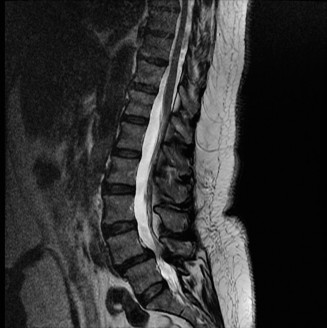

The correct answer is (A). As the case scenario strongly suggests an injury to the spine at the thoracolumbar junction, a CT scan of both the thoracic and lumbar regions is indicated. An MRI should not be the first imaging study obtained. Standing films should not be obtained in a trauma patient with a potentially unstable spine injury. A CT myelogram would only be obtained if an MRI was indicated but the patient had a contraindication to an MRI. Images of the above patient are shown inFigures 1–25 and 1–26. This injury is best characterized as which of the following? 1. Compression fracture

Figure 1–25

Figure 1–26

Discussion

The correct answer is (B). The images demonstrate an L1 vertebral body fracture with a small degree of kyphosis. There is comminution of the vertebral body with a posterior vertebral body fragment that is slightly retropulsed into the spinal canal. This separate posterior vertebral body fragment (which is noncontiguous with the pedicles) is the hallmark of a burst fracture. Compression fractures do not have any posterior vertebral body involvement. A Chance fracture, also known as a seat belt fracture or flexion–distraction injury, will exhibit distraction of the posterior elements through bone, bone-ligament, or purely ligament structures, with an axis of rotation somewhere within the anterior vertebral body or anterior to the vertebral body. A fracture dislocation exhibits translational deformities between the injured levels. While there appears to be a translational deformity on the sagittal CT, the vertebral bodies of the uninjured levels above and below are actually well aligned.